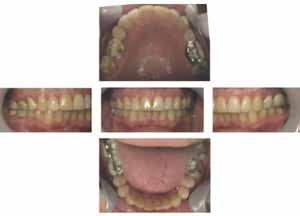

A hipertrófiás gonialis szögek a felszíni masseter izmok kétoldali gyakori és folyamatos összehúzódásainak következményei, amelyek fokozott hypercapneával járnak együtt (megnő a CO a vérben) [14-15]. A hypercapnoe az OSAban a légzésre való ingerlés. A páciens gonialis szögének hipertrófiája jól látható volt a felvételen (6. ábra). Az okkluzális analízis II. osztályú volt, bruxizmusból eredő attrícióval. Standard fényképfelvételeket is készítettek (7. ábra). A páciensnél egy szakképesítéssel rendelkező alvásszakértő orvos poliszomnográfiát (PSG) alkalmazva súlyos OSA-t diagnosztizált. Apnoe/ hypopnoe-indexe (AHI) 79,9 volt (az AHI 30

7. ábra: Okklúziós analízis: II. osztályú bruxizmus okozta kopással. 8. ábra: Az elzáródás 4 pontjának diagramja (Brett Streed illusztrációja).